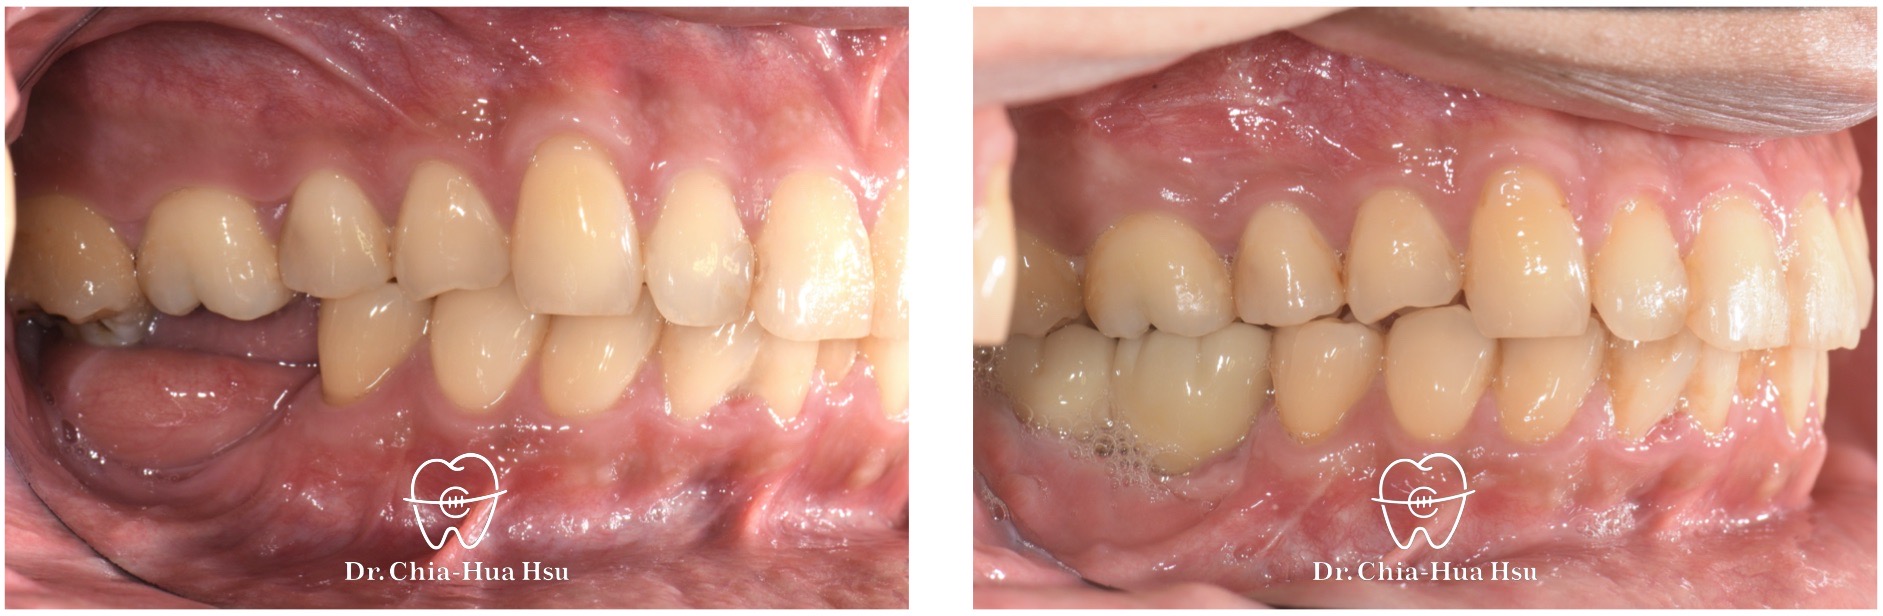

治療前

治療後

• 治療過程:治療過程中,上顎頰側及顎側使用骨釘與骨板,配合局部金屬矯正器,將後牙往上壓入齒槽骨。把咬合平面拉齊後,下顎騰出植牙與製作假牙的空間。

治療中